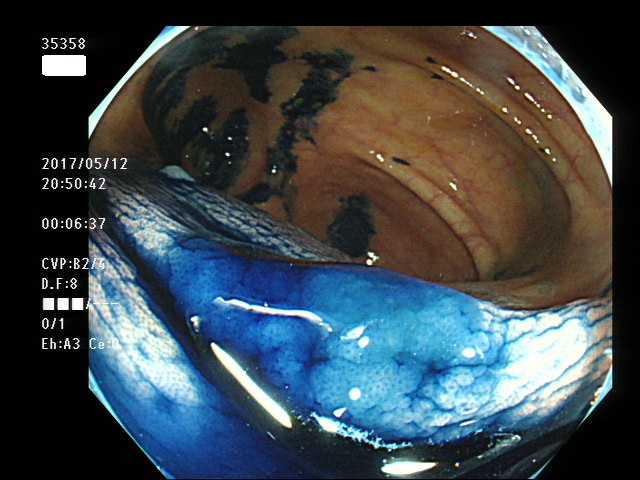

右側に大型の過形成(SSAP)が数個、多発する。SSAPが直接、癌化すると考えられている